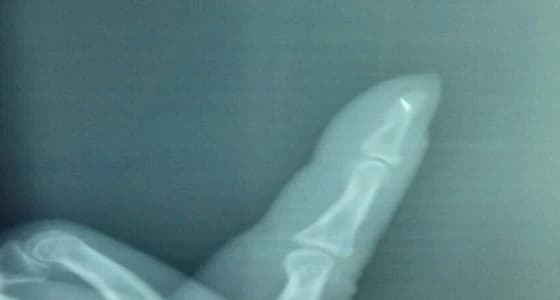

تمكن استشاري الجراحة الدكتور مجدي حسين، باستخراج إبرة طولها 2 مم من يد امرأة تبلغ من العمر 68 عاما، بعد خضوعها لعملية استغرقت 22 دقيقة في عيادة جراحة اليوم الواحد.

ولجأت المرأة في مهد الذهب إلى المستشفى، وهي تعاني من آلام شديدة في سبابة اليد اليمنى، مشيرة إلى أن نوبات الألم تلازمها في هذا الموضع منذ قرابة ٤٠ سنة؛ ولكنها اشتدت عليها مؤخراً.

وأكد الدكتور " حسين " ، خضوع المريضة للتشخيص، وبعد فحوصات من الفريق الطبي وعمل الأشعة، تبين وجود بقايا إبرة خياطة، استقرت في يدها منذ أربعين عاماً.